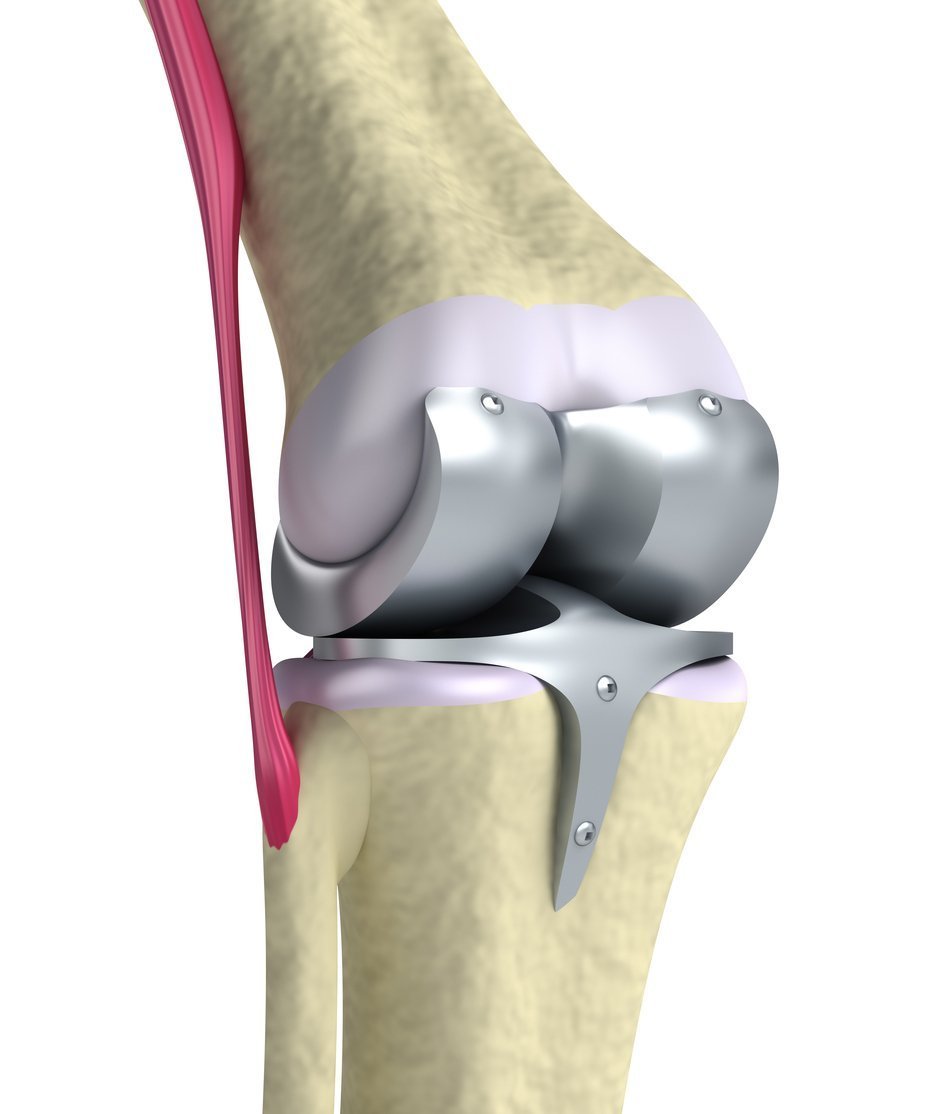

Total Knee Replacement

Total Knee Replacement

However, in the cases that don’t last as long as planned there are options for the patient to receive a revision of a total knee replacement. You and your doctor both could decide that the best plan of action would be to undergo a Revision Total Knee Replacement. The unfortunate part of the revision is that this surgery will be longer and more complex than the initial replacement. The need for revision could stem from a few different reasons.

The most common would be loosening or damage to the components of the prosthesis. Other reasons for the need for a revision for a total knee replacement would be:

During the procedure your orthopedic surgeon will assess what components from the original surgery need to be removed. First, the implants are inspected, and the damaged ones removed. Then, the surgeon will prepare the bone surface for the revision of the implant. In some cases, a bone graft may be used to help rebuild the knee. Once the implant has been placed in your knee, the doctor will be able to test the motion of the joint.